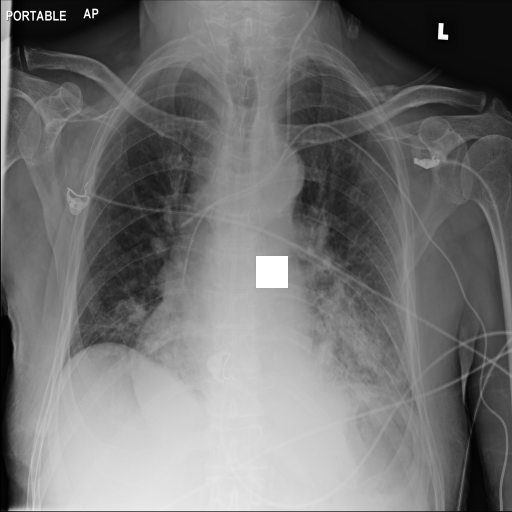

7.2 Qualitative assessment of LDP-processed CXR images

Here, we assume two possible privacy leakage scenarios. To CXR images, we intentionally add features that can lead to the re-identification of the subject appearing in a CXR image. The first feature is an artificial block marker. The second feature is a rare anatomical abnormality known as situs inversus simulated by flipping a CXR image along the vertical axis. Figs. 3(a) and 3(c) show CXR images with the artificial block marker. Fig. 5(a) shows a flipped CXR image to represent a case of situs inversus. We applied DP-GLOW to these CXR images. In Figs. 3(b) and 3(d), the image domain LDP fails to obfuscate the artificial block marker with a moderate privacy budget. In contrast, in Figs. 4(b) and 4(d), DP-GLOW successfully obfuscated the artificial block marker with the moderate privacy budget. On the other hand, the anatomical shape of the chest and the abnormal opacity (hilar regions in the case 1) are preserved. In Fig. 5(b), we observed that the right edge of the heart does not become obfuscated with the image domain LDP. In contrast, in Fig. 6(b), we observed that the right edge of the heart becomes obfuscated and the heart appears at the center of the thoracic cage with DP-GLOW. However, DP-GLOW with this privacy budget is insufficient to almost completely erase the feature of situs inversus.